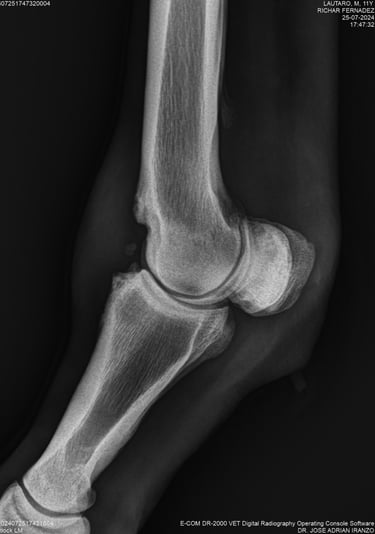

DIAGNOSTICO POR IMAGENES: ECOGRAFIA Y RADIOGRAFIA